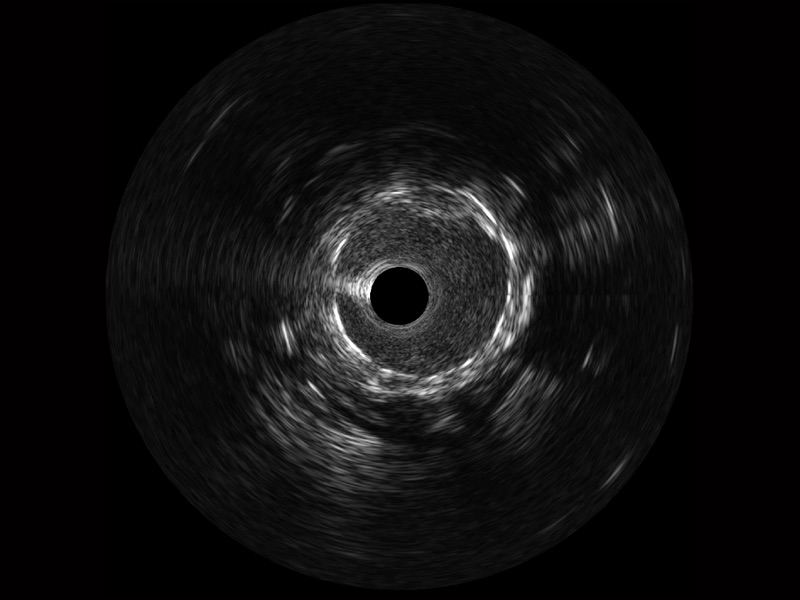

银河集团官网宽频IVUS图像

传统IVUS图像

对比传统IVUS导管成像,银河集团官网宽频IVUS图像的近场支架梁显影更细腻,远场中膜外血管仍清晰可辨,兼顾远中近,兼顾分辨力与穿透深度